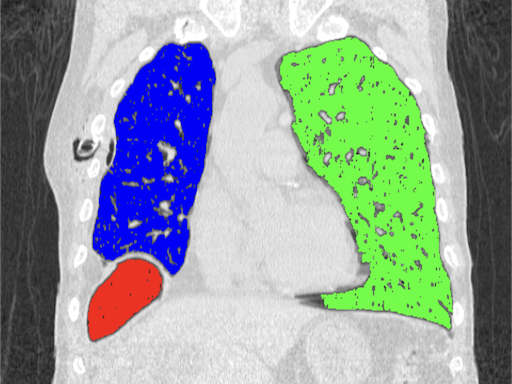

Segmentation refers to the division of an image into multiple segments or regions based on certain characteristics, such as color, intensity, texture, or edges. Its purpose is to simplify the representation of images for analysis and understanding by dividing them into reasonable parts.

An iterative clustering method that can be used for image segmentation. The algorithm randomly selects K centroids, then assigns each pixel to the closest cluster based on pixel intensity or other features. Then, the algorithm calculates new centroids based on the average position of the pixels in each cluster. This process is repeated until cluster centers no longer change significantly. Pixels with similar properties are grouped into clusters so that different regions can be separated.